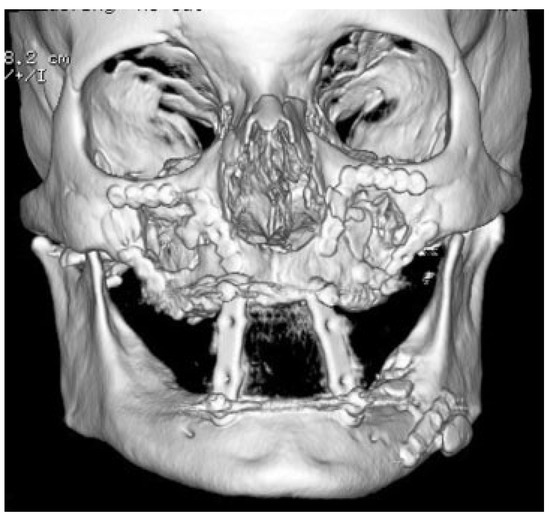

A Novel Technique for Attaining Maxillomandibular Fixation in the Edentulous Mandible Fracture

:Case Report